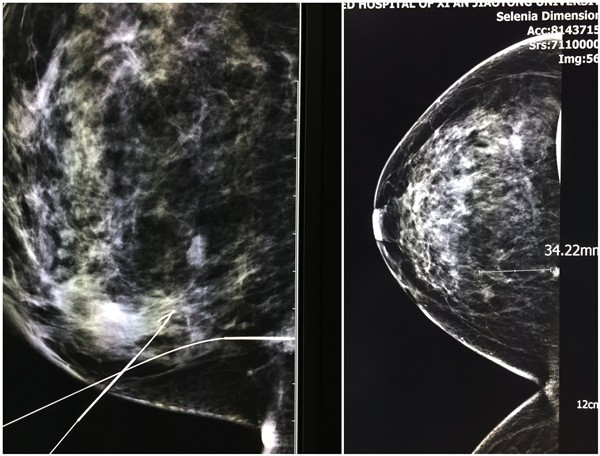

11月8日,我院医学影像科经精心准备,在陈欣副主任的主导下,顺利完成了我院首例单侧乳腺同象限两处微小钙化的乳腺X线affirm3D自动定位技术引导下穿刺定位术,准确锁定了病灶,这不仅标志着我院医学影像科自引进美国Hologic数字乳腺钼靶机后三维立体定位穿刺术又迈上了一个新台阶,更为临床隐匿性乳腺癌的精准诊断、治疗提供了坚实的基础。

据悉,本次接受穿刺的是一位38岁女性患者,因双侧乳头溢液收治入院,入院后钼靶检查发现右乳内下象限两处簇状不定形钙化,两处仅相距3.4厘米,由于钙化小,病变深在,触诊阴性,术中难以准确定位,为了精确切除病灶,在我院肿瘤病院刘晓旭教授、管海涛教授及马小斌副教授建议下,决定实施乳腺X线affirm3D自动定位技术引导下穿刺定位。陈欣副主任与晋瑞主治医生经过细致规划,术前多次调整进针方向及深度,在戚威主治医师及杨慧技师通力配合下,在短时间内,分别经内外侧斜位和侧位入路,一次性定位,准确的将导丝伞端送至钙化处。